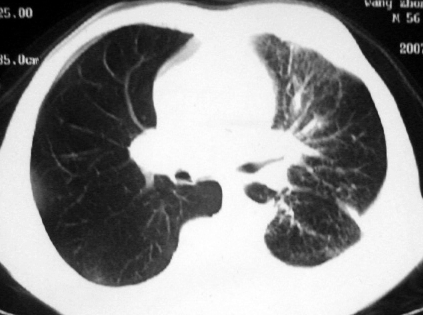

男,54岁,咳嗽,气喘半年,胸痛一月.

血性胸水

左侧胸腔积液 斜裂积液 心包积液 左肺不张 考虑左肺ca并胸膜心包转移。

支持左肺下叶中心型肺癌(累及舌叶)伴阻塞性肺炎、膨胀不全、胸腔积液、心包少量积液。

考虑左肺下叶中央型肺癌伴阻塞性肺炎及肺不张,纵隔受累可能,胸膜转移。

左肺下叶中心型肺癌,伴阻塞性肺炎、左胸腔积液、心包少量积液。

1.左肺下叶中心性肺癌伴阻塞性肺炎,肺不张.

2.左侧胸腔积液,心包积液